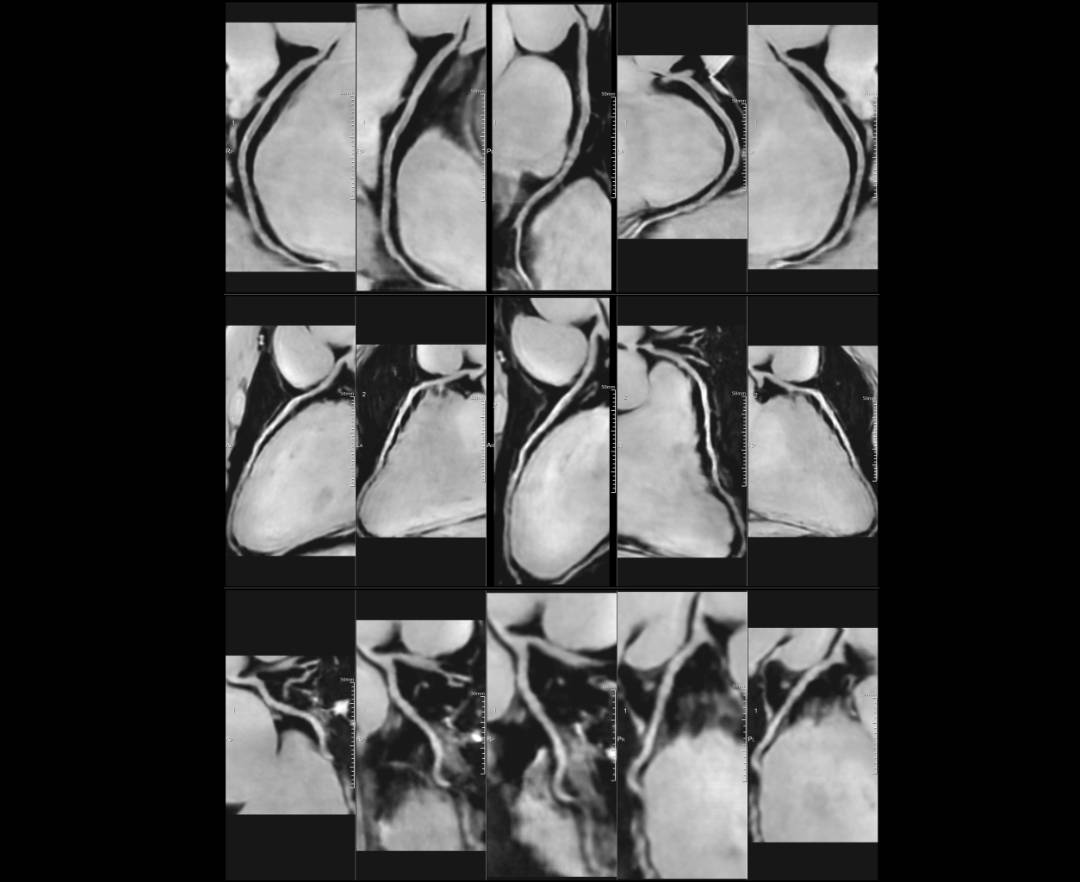

MRCA HRR*

MRCA*

*MRCA HRR & MRCA were Post-Processed by uOmnispace